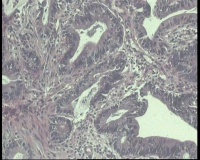

急!请老师帮忙看看,单位同事肠镜病理

进镜达横结肠近肝曲,见不规则增生性肿物,环周生长,表面充血糜烂,触之易出血,肠腔狭窄,镜身无法通过

肠镜活检4块

镜下腺体异型小,纤维间质反应,能直接报结肠腺癌吗?

可一类报告报:管状绒毛状腺癌

高-中分化腺癌。